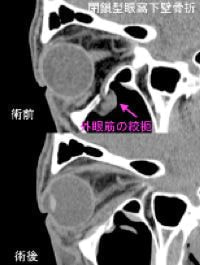

●眼窩壁骨折